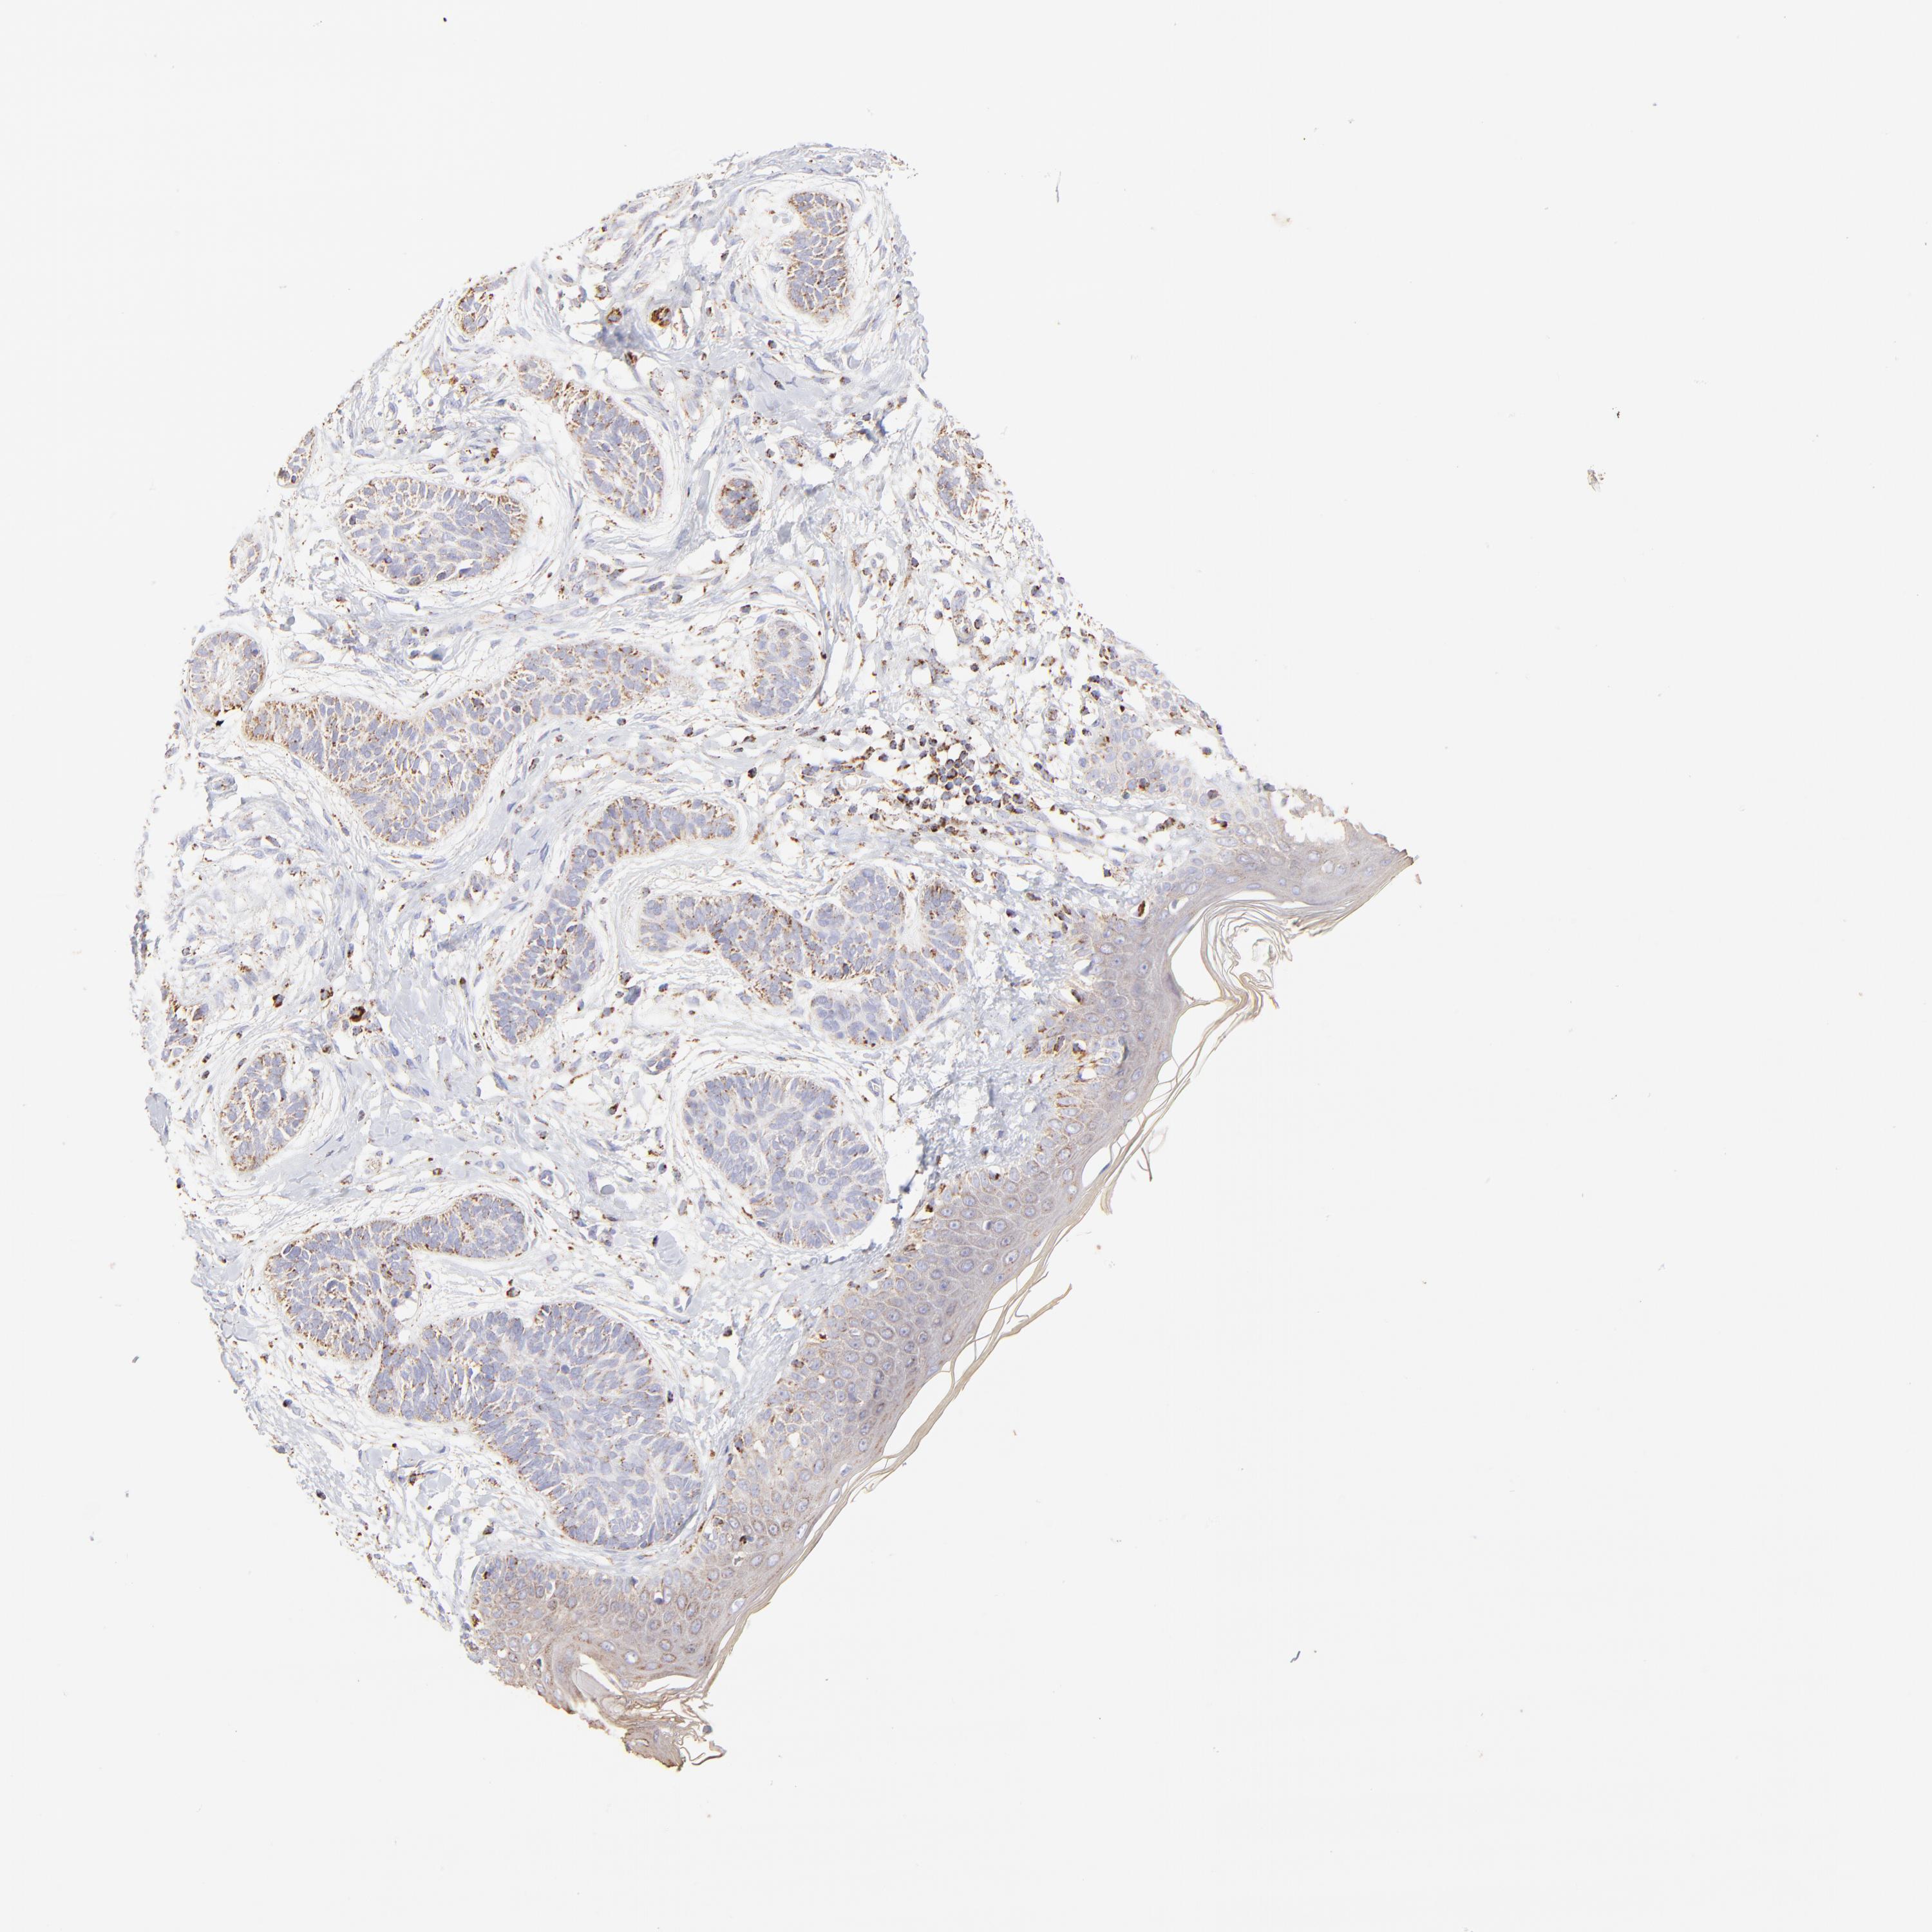

SKIN CANCER - Protein expressioni

A mouse-over function shows sample information and annotation data. Click on an image to view it in a full screen mode. Samples can be filtered based on level of antibody staining by selecting one or several of the following categories: high, medium, low and not detected. The assay and annotation is described here.

Antibody stainingi

Antibody staining in the annotated cell types in the current human tissue is reported as not detected, low, medium, or high, based on conventional immunohistochemistry profiling in selected tissues. This score is based on the combination of the staining intensity and fraction of stained cells.

Each image is clickable and will lead to virtual microscopy that enables deeper exploration of all samples and also displays staining intensity scores, fraction scores and subcellular localization as well as patient and tissue information for each sample.

Antibody HPA005835

Squamous cell carcinoma, NOS